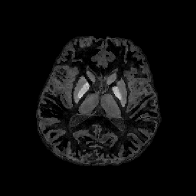

Table 1 summarizes the relative error and the SSIM of the direct approaches (Eqs. 1.5 and 1.6) and the wavelet frame regularization approaches, and Figs. 8 and 9 present visual comparisons of the results. In addition, Table 2 summarizes the aforementioned indices of the direct approaches and the TGV regularization approaches, and Figs. 10 and 11 depict the visual comparisons. We can see that both the Frame-HIRE and the TGV-HIRE consistently outperform the existing direct approaches, the integral approaches, and the differential approaches in both cases. At first glance, this verifies the convention that the regularization based models in general performs better in solving the ill-posed inverse problem of QSM than the direct methods [27, 51]. Most importantly, this result demonstrates that the measured local field data obtained from the phase of a complex GRE MR signal contains the harmonic incompatibility other than the noise, which agrees with our theoretical discovery, and the performance gain mainly comes from taking both the noise in the measured data and the harmonic incompatibility (the incompatibility other than the noise) at the same time. Meanwhile, since this harmonic incompatibility is not taken into account in the integral approaches, the reconstructed susceptibility images contain the shadow artifacts as shown in Figs. 8d, 9d, 10d and 11d. The differential approaches can remove the harmonic incompatibility in the measured data in advance, leading to the shadow artifact removal compared to the integral approach. However, since the noise in blsubscript𝑏𝑙b_{l} was amplified by {\mathscr{L}}, the final reconstructed images contain the streaking artifacts as shown in Figs. 8e, 9e, 10e and 11e, leading to the degradation in indices at the same time.

Figure 8: Sagittal slice images comparing QSM reconstruction methods for the brain phantom experiments. All sagittal slice images of brain phantom experimental results are displayed in the window level [0.03,0.07]0.030.07[-0.03,0.07] for the fair comparison.

Figure 9: Axial slice images comparing QSM reconstruction methods for the brain phantom experiments with the wavelet frame regularization. All axial slice images of brain phantom experimental results are displayed in the window level [0.03,0.19]0.030.19[-0.03,0.19] for the fair comparison.

Figs. 14 and 15 display the visual comparisons of the direct approaches and the wavelet frame regularization approaches, and the zoom-in views of Fig. 14 are provided in Fig. 16. We also provide the visual comparisons of the direct approaches and the TGV regularization approaches in Figs. 17, 18 and 19. Since the reference image is not available for in vivo MR data, it is in general more difficult to provide quantitative evaluations than the numerical brain phantom. Nonetheless, we can see from the viewpoint of visual comparison that the pros and cons are almost the same as the numerical brain phantom experiments. It is also worth noting that the HIRE models can reduce the streaking artifacts which propagate from ΩΩ\partial\Omega into ΩΩ\Omega as well as the shadow artifacts. As pointed out in [52], the in vivo local field data is prone to the outliers near ΩΩ\partial\Omega because the GRE signal lacks information outside ΩΩ\Omega. Hence, we can see that most streaking artifacts propagate from these outliers near ΩΩ\partial\Omega into the ROI. However, thanks to the sparsity promoting property of 1subscript1\ell_{1} norm, the term λv1𝜆subscriptnorm𝑣1\lambda\left\|{\mathscr{L}}v\right\|_{1} in the HIRE approaches can somehow capture and remove them, leading to the suppression of artifacts propagating from ΩΩ\partial\Omega into ΩΩ\Omega as well as the shadow and streaking artifact removal. Finally, even though we can also note that the Tikhonov regularization can somehow reduce the artifacts, there are some losses of features due to the smoothness prior of the susceptibility image.

Figure 14: Sagittal slice images comparing QSM reconstruction methods for the in vivo MR data experiments with the wavelet frame regularization. All images of in vivo MR data experimental results are displayed in the window level [0.2,0.2]0.20.2[-0.2,0.2] for the fair comparison.

Figure 15: Axial slice images comparing QSM reconstruction methods for the in vivo MR data experiments with the wavelet frame Regularization.